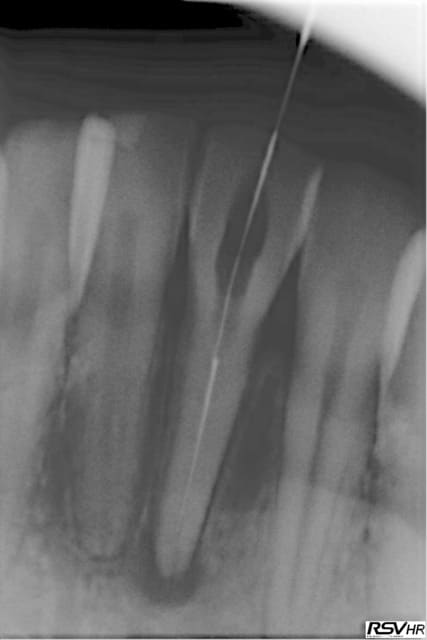

Le patient a 29 ans, je remarque une dyschromie sur une 41 totalement asymptomatique, radio et je trouve une lésion apicale.

Je décide donc de faire l'endo. La chambre était relativement basse, j'ouvre et je commence à aléser avec une lime 10. Et elle casse...

Radio msvndw - Eugenol

pour ton cas, je pense qu'il faut essayer avec tes limes endosonores de passer à coté (avec un peu de bol tu as un canal en 8... fréquent que les incisives en bas)

Ensuite c'est une lime 10 (fine et a priori qui n'a pas été trop vissée puisque manuelle) cassée haut dans un canal, donc tu passes gates 3 à l'entrée du canal, puis gates 2 sur 1 ou 2mm puis le un jusqu'à voir distinctement l'instrument. Après ça tu acchètes un insert endo droit (non diamanté hein!) et tu te mets aux alentours de 30%-50% de la puissance de ton unit et tu vas au contact de l'instrument, mais sans appuyer (tu risques d'enfoncer la lime plus loin. Normalement après peu de temps (5-10 minutes surement) ça devrait sortir. Ne pas s'énerver, jamais en endo!